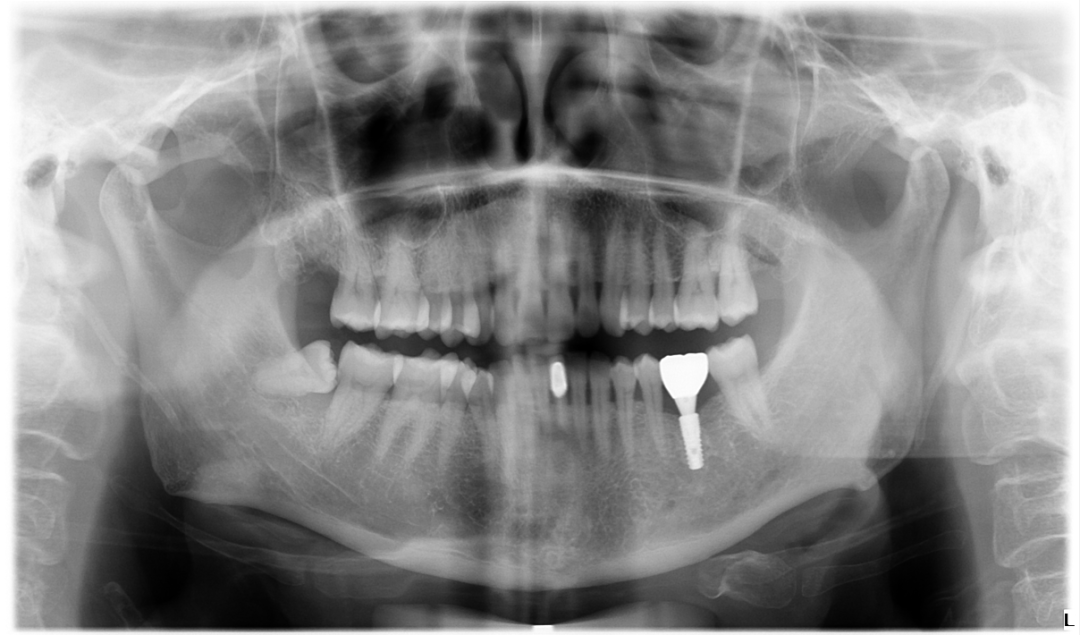

第一步,郑主任为胡女士拍摄了口腔CT,检查了口腔环境,设计了种植方案,选择了手术日期。

第二步,植入植体。在高标准层流种植手术间里将种植体植入到胡女士缺牙区的牙槽骨中,然后缝合。

最新引进口腔CT(CBCT),CBCT是口腔科专用CT,具有扫描快、范围大、精度高、应用广、放射剂量极低的特点。可以通过其强大的处理软件功能以及面部匹配技术迅速形成清晰逼真的三维图像,在智齿拔除、牙种植测量、多生牙定位、颞下颌关节疾病、颌骨三维重建、根管治疗评估、正畸设计等方面提供精准的诊断与治疗依据。